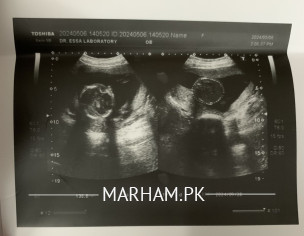

Salam, I am just about to complete my 20 weeks pregnancy journey, and my doctor asked me to do an anomaly scan. The ultrasound technician told me that I’m having a baby boy, but I’ve some doubts because I’ve heard that women with anterior placenta are mostly pregnant with baby girls. Can somebody please tell me by taking a look at my ultrasound pictures that am I having a baby boy or a baby girl? And is everything normal in my anomaly scan? Thank you in advance!

it's a myth , placement of placenta has nothing to do with gender.. you pics are not uploading??